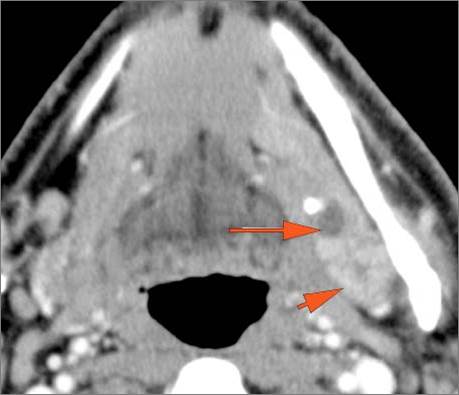

9 month old male presenting to the emergency room with poor feeding, fever, respiratory distress and possible retropharyngeal abscess or suppurative retropharyngeal adenitis.Exam

There is excessive enhancement or thickening of the mucosa or hypertrophy of the palatine or lingual tonsillar tissue or the lymphoid tissue along the glossotonsillar sulci and posterior pharyngeal wall. |

Yes | NA |

There is reactive retropharyngeal lymphadenopathy. |

There is suppurative retropharyngeal lymphadenopathy. |

If there is suppurative retropharyngeal adenopathy what is the maximum short axis dimension of the largest suppurative node. Measurement |

< 2cm | NA |

There is edema/abscess within the adjacent parapharyngeal and retropharyngeal spaces. |

Pharyngitis with suppurative retropharyngeal adenitis.